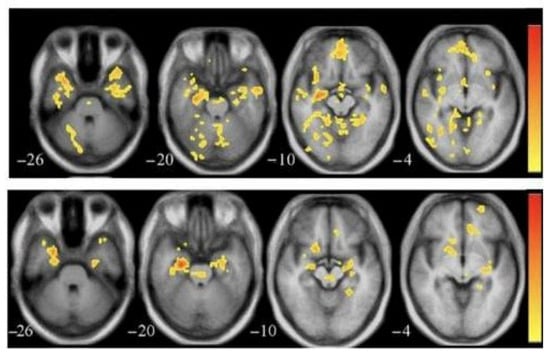

3.6. Diffusion Tensor Imaging (DTI)